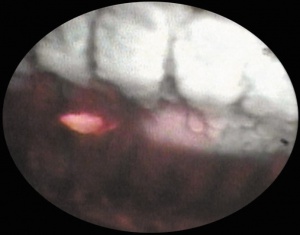

One of the great advantages of ECP over transscleral cyclophotocoagulation techniques is the ability to deliver laser energy in a highly titratable fashion to the ciliary processes. The optimum tissue effect is to whiten the ciliary process and effect visible tissue shrinkage. Photocoagulation is applied with the endoscope 1.0–3.0 mm from the ciliary processes. Kahook, Noecker, and colleagues recommend lasering with a distance of about 2 mm from the ciliary processes. From this distance one can usually see 6 ciliary processes in the field of view of the endoscope (see corresponding figure to right). This distance is ideal for minimizing laser energy transmission loss while also minimizing the risk of overtreatment.[12] The power levels of the 810-nm semiconductor diode laser are titrated upward from lower power levels to achieve whitening and shrinkage of the ciliary processes (see corresponding figure to right). Usually 100-300 mW is all that is required to achieve the desired effect on tissues. A slow continuous wave application of the laser treatment allows surgeons to methodically “paint” the entirety of each ciliary process in a smooth, well-controlled fashion. Treatment of at least 270° is often required to get optimal intraocular pressure reduction with ECP.[13] If administering ECP through one incision, the curved endoscope probe enhances a surgeon’s ability to expand the ciliary process treatment area beyond what can be accomplished with a straight endoscope. Kahook and colleagues showed that 360 degrees of treatment with ECP through two incisions is superior to partial treatment through one incision. 360 degree treatment produced lower IOP, gave greater reduction in glaucoma medication burden, and had fewer treatment failures than partial treatment.[13]